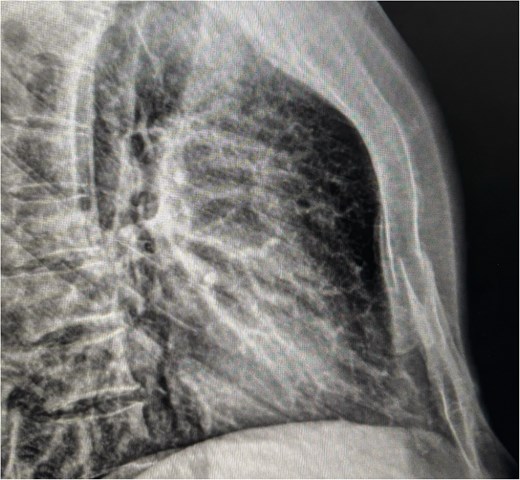

Chest radiographs demonstrated an oblique fracture of the mid-sternum, indicated by a discontinuity in the anterior and posterior cortical surfaces (Fig. 1). Additionally, a 3D CT scan confirmed the presence of a non-displaced oblique fracture (Fig. 2) and revealed a sternal foramen adjacent to the fracture site (Fig. 3). This anatomical variation raised concerns of a potential mediastinal injury in the event of fracture displacement or during surgical intervention.

Lateral chest X-ray showing cortical discontinuity in the midportion of the sternal body (red arrow), indicative of an oblique fracture.